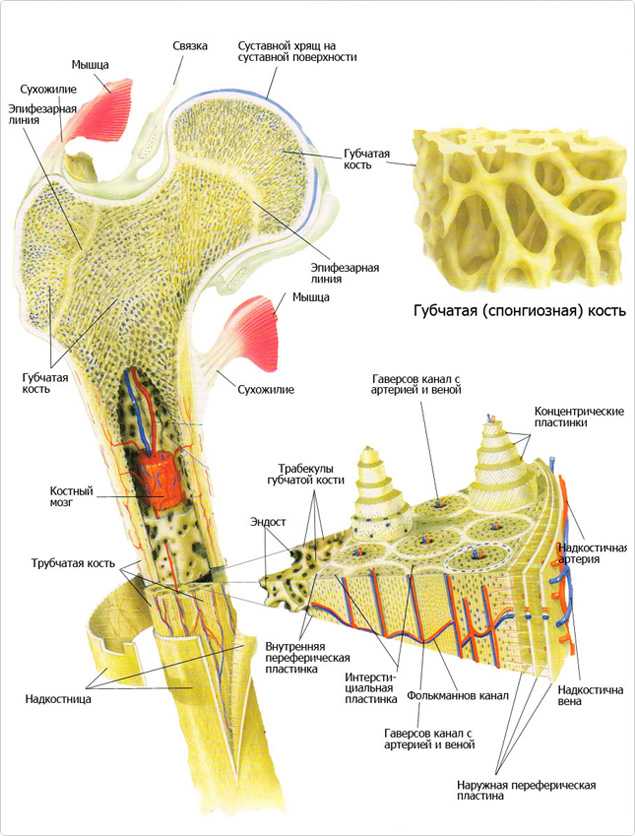

Структура костной ткани и кровообращение

Структура костной ткани

Кость состоит из костного вещества, костного мозга и надкостницы, а также имеет разветвленную сеть кровеносных сосудов и нервов, как показано на рисунке. Длинная бедренная кость состоит из диафиза и двух выпуклых эпифизарных концов. Поверхность каждого эпифизарного конца покрыта хрящом и образует гладкую суставную поверхность. Коэффициент трения в пространстве между хрящами в месте соединения сустава очень мал, он может быть ниже 0.0026. Это самый низкий известный показатель силы трения между твердыми телами, что позволяет хрящу и соседним костным тканям создать высокоэффективный сустав. Эпифизарная пластинка образована из кальцинированного хряща, соединенного с хрящом. Диафиз представляет собой полую кость, стенки которой образованы из плотной кости, которая является довольно толстой по всей ее длине и постепенно утончающейся к краям.

Костный мозг заполняет костномозговую полость и губчатую кость. У плода и у детей в костномозговой полости находится красный костный мозг, это важный орган кроветворения в человеческом организме. В зрелом возрасте мозг в костномозговой полости постепенно замещается жирами и образуется желтый костный мозг, который утрачивает способность к кроветворению, но в костном мозге по-прежнему имеется красный костный мозг, выполняющий эту функцию.

Надкостница представляет собой уплотненную соединительную ткань, тесно прилегающую к поверхности кости. Она содержит кровеносные сосуды и нервы, выполняющие питательную функцию. Внутри надкостницы находится большое количество остеобласта, обладающего высокой активностью, который в период роста и развития человека способен создавать кость и постепенно делать ее толще. Когда кость повреждается, остеобласт, находящийся в состоянии покоя внутри надкостницы, начинает активизироваться и превращается в костные клетки, что имеет важное значение для регенерации и восстановления кости.

Микроструктура кости

Костное вещество в диафизе большей частью представляет собой плотную кость, и лишь возле костномозговой полости имеется небольшое количество губчатой кости. В зависимости от расположения костных пластинок, плотная кость делится на три зоны, как показано на рисунке: кольцевидные пластинки, гаверсовы (Haversion) костные пластинки и межкостные пластинки.

Кольцевидные пластинки представляют собой пластинки, расположенные по окружности на внутренней и внешней стороне диафиза, и они подразделяются на внешние и внутренние кольцевидные пластинки. Внешние кольцевидные пластинки имеют от нескольких до более десятка слоев, они располагаются стройными рядами на внешней стороне диафиза, их поверхность покрыта надкостницей. Мелкие кровеносные сосуды в надкостнице пронизывают внешние кольцевидные пластинки и проникают вглубь костного вещества. Каналы для кровеносных сосудов, проходящие через внешние кольцевидные пластинки, называются фолькмановскими каналами (Volkmann’s Canal). Внутренние кольцевидные пластинки располагаются на поверхности костномозговой полости диафиза, они имеют небольшое количество слоев. Внутренние кольцевидные пластинки покрыты внутренней надкостницей, и через эти пластинки также проходят фолькмановские каналы, соединяющие мелкие кровеносные сосуды с сосудами костного мозга. Костные пластинки, концентрично расположенные между внутренними и внешними кольцевидными пластинками, называются гаверсовыми пластинками. Они имеют от нескольких до более десятка слоев, расположенных параллельно оси кости. В гаверсовых пластинках имеется один продольный маленький канал, называемый гаверсовым каналом, в котором находятся кровеносные сосуды, а также нервы и небольшое количество рыхлой соединительной ткани. Гаверсовы пластинки и гаверсовы каналы образуют гаверсову систему. Вследствие того, что в диафизе имеется большое число гаверсовых систем, эти системы называются остеонами (Osteon). Остеоны имеют цилиндрическую форму, их поверхность покрыта слоем цементина, в котором содержится большое количество неорганических составных частей кости, костного коллагенового волокна и крайне незначительное количество костного матрикса.

Межкостные пластинки представляют собой пластинки неправильной формы, расположенные между остеонами, в них нет гаверсовых каналов и кровеносных сосудов, они состоят из остаточных гаверсовых пластинок.

Внутрикостное кровообращение

В кости имеется система кровообращения, например, на рисунке показа модель кровообращения в плотной длинной кости. В диафизе есть главная питающая артерия и вены. В надкостнице нижней части кости имеется маленькое отверстие, через которое внутрь кости проходит питающая артерия. В костном мозге эта артерия разделяется на верхнюю и нижнюю ветви, каждая из которых в дальнейшем расходится на множество ответвлений, образующих на конечном участке капилляры, питающие ткани мозга и снабжающие питательными веществами плотную кость.

Кровеносные сосуды в конечной части эпифиза соединяются с питающей артерией, входящей в костномозговую полость эпифиза. Кровь в сосудах надкостницы поступает из нее наружу, средняя часть эпифиза в основном снабжается кровью из питающей артерии и лишь небольшое количество крови поступает в эпифиз из сосудов надкостницы. Если питающая артерия повреждается или перерезается при операции, то, возможно, что снабжение кровью эпифиза будет заменяться на питание из надкостницы, поскольку эти кровеносные сосуды взаимно связываются друг с другом при развитии плода.

Кровеносные сосуды в эпифизе проходят в него из боковых частей эпифизарной пластинки, развиваясь, превращаются в эпифизарные артерии, снабжающие кровью мозг эпифиза. Есть также большое количество ответвлений, снабжающих кровью хрящи вокруг эпифиза и его боковые части.

Верхняя часть кости представляет собой суставный хрящ, под которым находится эпифизарная артерия, а еще ниже ростовой хрящ, после чего имеются три вида кости: внутрихрящевая кость, костные пластинки и надкостница. Направление кровотока в этих трех видах кости неодинаково: во внутрихрящевой кости движение крови происходит вверх и наружу, в средней части диафиза сосуды имеют поперечное направление, а в нижней части диафиза сосуды направлены вниз и наружу. Поэтому кровеносные сосуды во всей плотной кости расположены в форме зонтика и расходятся лучеобразно.

Строение кости

Компактное вещество кости формируют костные пластины, плотно прилегающие друг к другу и образующие остеоны (структурные единицы компактного вещества костной ткани). Компактное вещество придает кости прочность.

Губчатое вещество также содержит костные пластинки, однако они не образуют остеоны, в связи с чем губчатое вещество менее прочное, чем компактное вещество. В губчатом веществе между костными перекладинами (костными балками) расположен красный костный мозг.

Основные клетки костной ткани, изученные нами в разделе «соединительные ткани»: остеобласты, остеоциты и остеокласты. Остеоциты имеют отростчатую форму и располагаются вокруг Гаверсова канала.